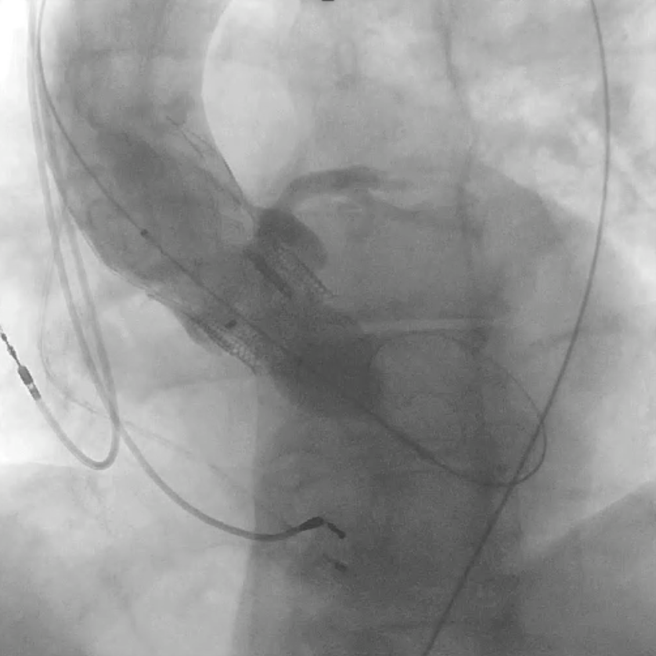

Операция выполнялась руководителем Отдела рентгенэндоваскулярных методов диагностики и лечения, главным научным сотрудником, д.м.н. Меркуловым Е.В., старшим научным сотрудником, к.м.н. Терещенко А.С. и научным сотрудником, к.м.н. Арутюнян Г.К. Клиническую подготовку и анестезиологическую поддержку обеспечивали сотрудники Отдела неотложной кардиологии (руководитель отдела - главный научный сотрудник, д.м.н. Певзнер Д.В.), а также сотрудники блока интенсивного наблюдения под руководством заведующего Зюряева И.Т. и врачей Кушнира П.Ф., Дулаева Л.О., Тереничевой М.А. Во время вмешательства осуществлялся ангиографический контроль проходимости коронарных артерий с раздуванием баллона в корне аорты. Эндоваскулярное вмешательство прошло без осложнений с хорошим клиническим результатом. У пациента полностью регрессировала недостаточность аортального клапана. Пациент с улучшением состояния был выписан из Отдела неотложной кардиологии НМИЦ кардиологии им. ак. Е.И. Чазова Минздрава России. За ним будет продолжено динамическое клиническое наблюдение.

Контроль проходимости коронарных артерий при раздутом баллонном катетере